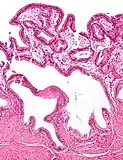

Micrograph of cholesterolosis of the gallbladder -

The name strawberry gallbladder comes from the typically stippled appearance of the mucosal surface on gross examination, which resembles a strawberry. Cholesterolosis results from abnormal deposits of cholesterol esters in macrophages within the lamina propria (foam cells) and in mucosal epithelium. The gallbladder may be affected in a patchy localized form or in a diffuse form. The diffuse form macroscopically appears as a bright red mucosa with yellow mottling (due to lipid), hence the term strawberry gallbladder. It is not tied to cholelithiasis (gallstones) or cholecystitis (inflammation of the gallbladder).[2]